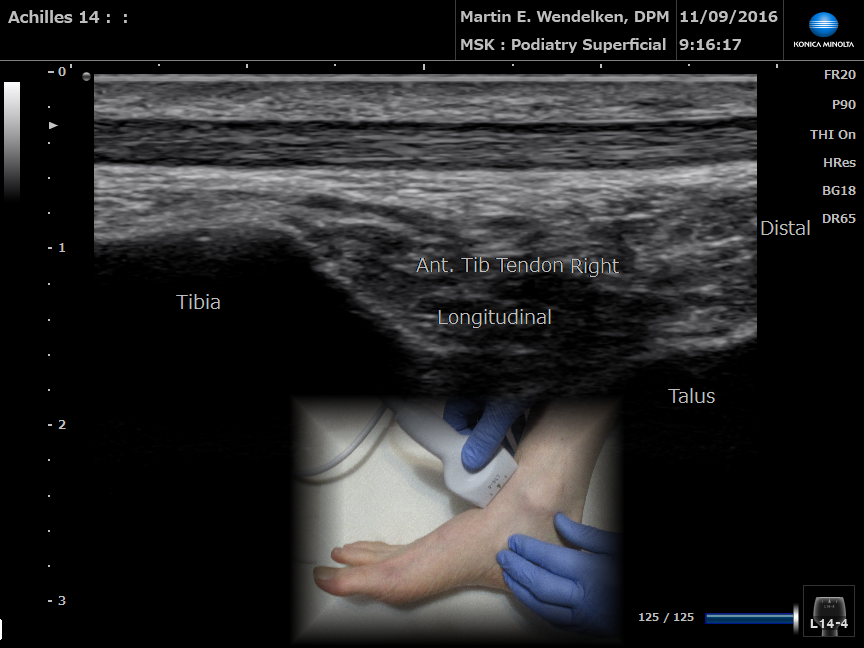

• Image 2: Achilles Tendon